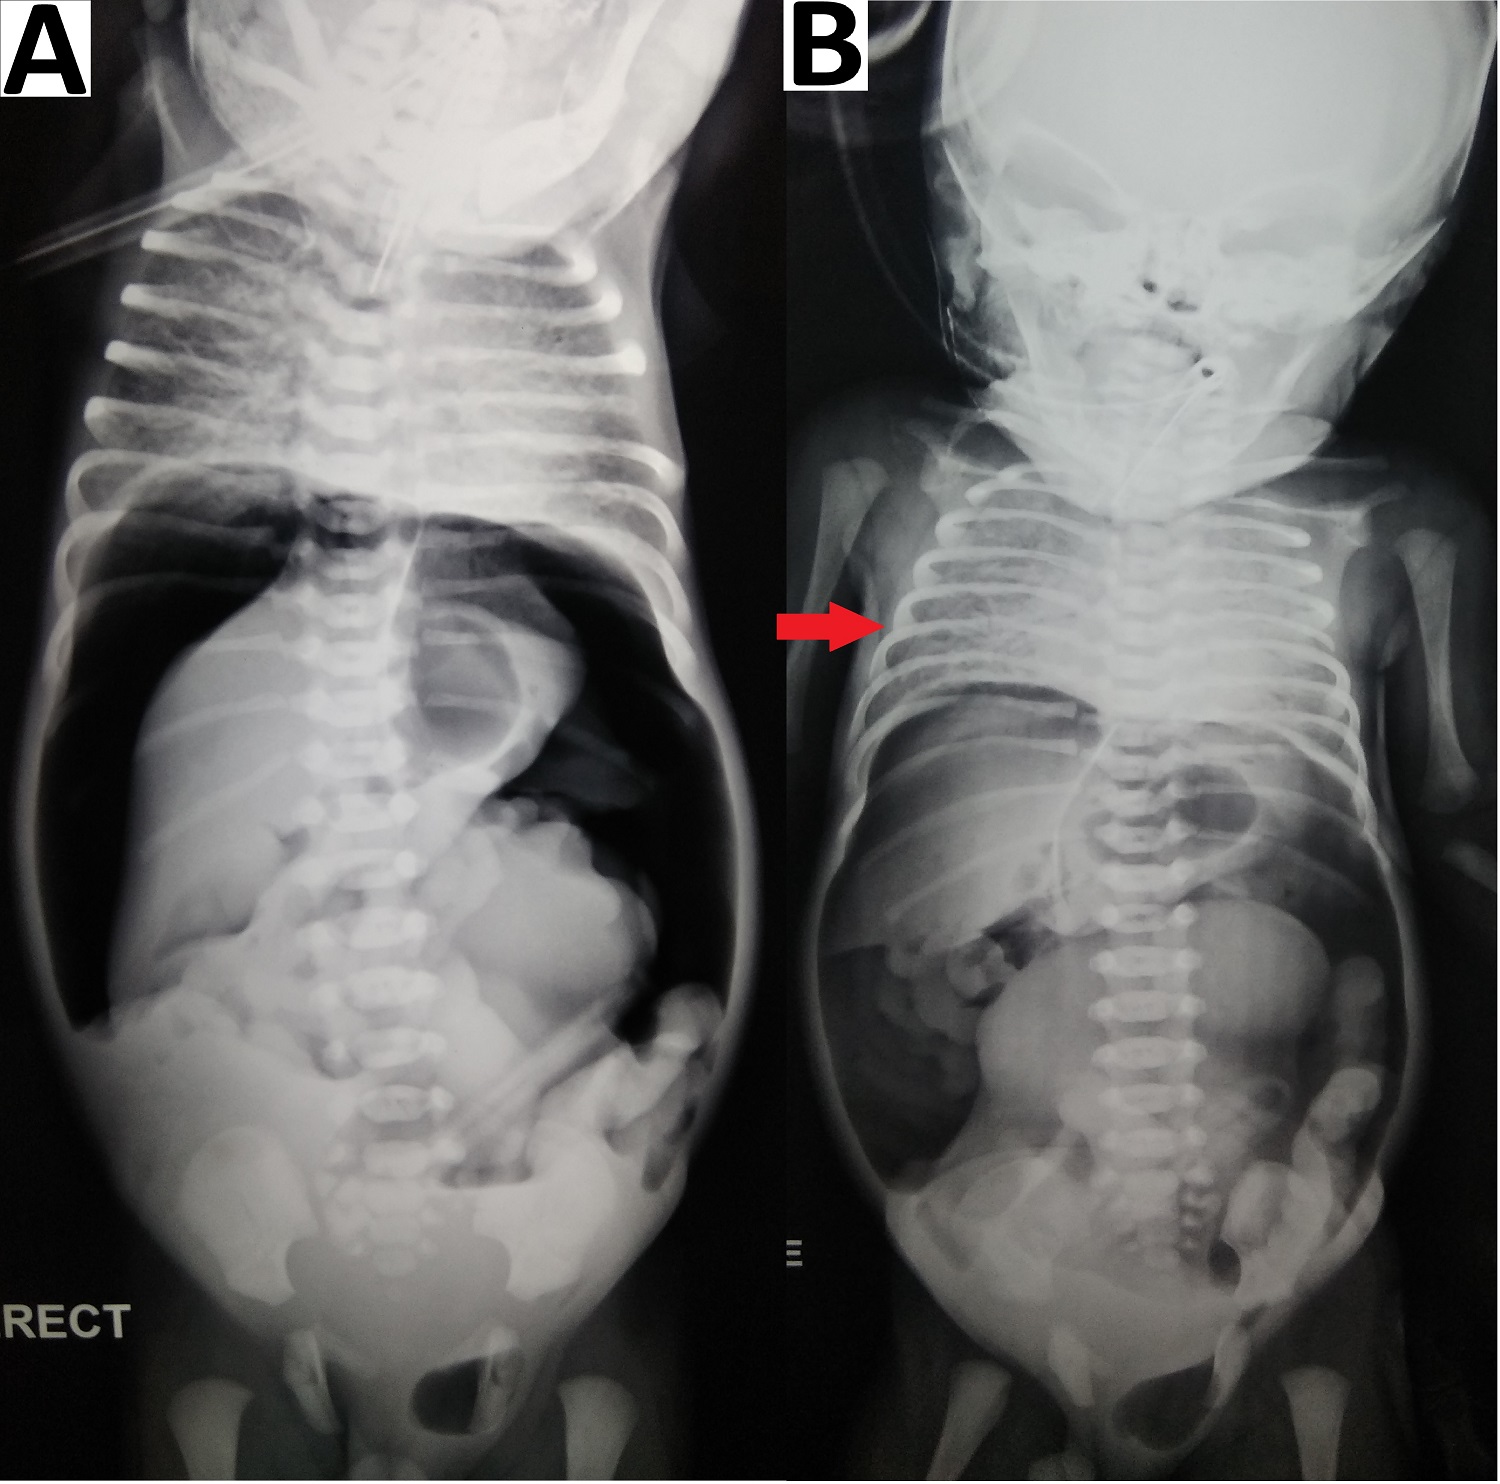

Figure 1

Abdominal radiographs (erect) (A) showing pneumoperitoneum with gas under the diaphragm (red arrows), Rigler sign (white arrows) and outlining of falciparum ligament (black arrow); supine image (B) showing Rigler sign (white arrows); erect image (C) showing resolution of pneumoperitoneum after abdominal drain placemen.

Pneumoperitoneum with air under both the domes of the diaphragm was seen in all 4 patients on erect abdominal radiographs (Fig. 1)(Fig. 2)(Fig. 3)(Fig. 4). There was an absence of free fluid in the peritoneal cavity evident by the absence of air-fluid level in the peritoneal (abdominal) cavity i.e. outside bowel loops in all the patients. Dilated small bowel loops were seen in 3 out of 4 patients. Rigler sign or double-wall sign was present in 3 patients. Radiographic evidence of pneumothorax (simultaneously present with pneumoperitoneum) was seen in 1 patient (Fig. 4). Pneumoscrotum was appreciated in 2 patients (Fig. 3)(Fig. 4).

Pneumoperitoneum in a neonate is classically due to GI perforation and necrotizing enterocolitis (NEC).[3], [4] Pneumoperitoneum is usually diagnosed by an erect abdominal radiograph showing free air under the domes of the diaphragm. In the neonates the other radiographic signs include, (a) rounded or oval lucency over the upper abdomen in the supine position, (b) increased lucency i.e. triangular or a semilunar collection of air anterior to the abdominal viscera or above the liver in lateral decubitus position, (c) large volume of free air may give rise to the football sign, where the air outlines the whole of the peritoneal cavity and under the surface of the diaphragm, (d) the lacing of the football i.e. outlining of falciparum ligament of the liver against the radiolucency of free abdominal air on supine view [4], [5], [6] (e) Rigler sign or double-wall sign is free gas on both sides of the bowel wall,[4], [5] (f) pneumoscrotum has been explained due to presence of patent processus vaginalis and passage of air from the peritoneal cavity into the scrotum.[3], [5], [6]